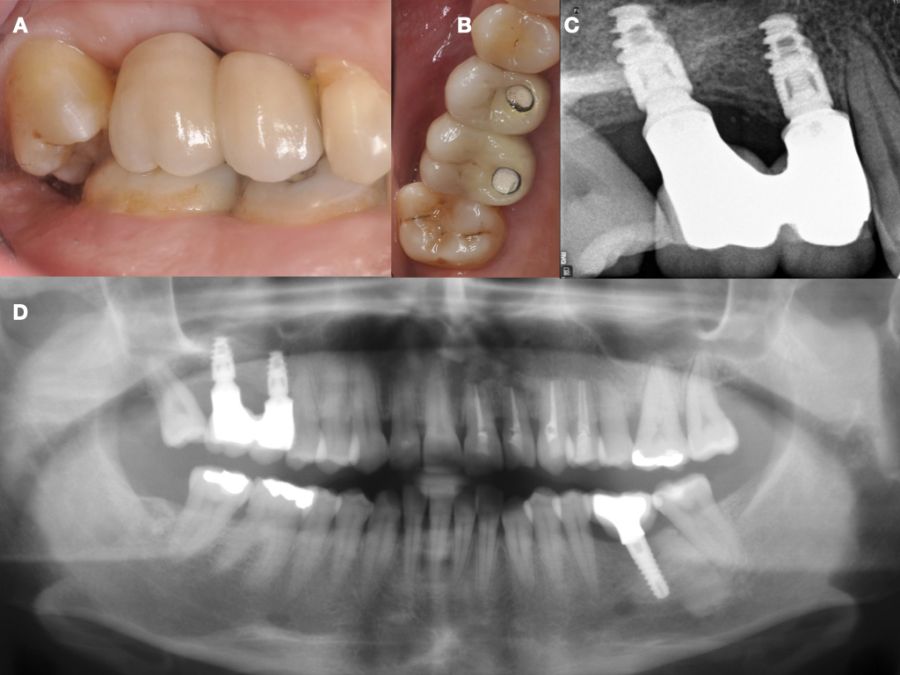

En la historia clínica, no se evidenciaron antecedentes médico-quirúrgicos de interés, alergias medicamentosas conocidas ni hábitos nocivos. A la exploración intraoral, se apreciaron las ausencias de 1.6 y 1.7 y la presencia del 1.8 y 4.8 (Figura 1). En la exploración radiográfica mediante escáner de haz cónico (CBCT) se apreció una altura residual de 5,0 mm en 1.6, donde se podría colocar un implante simultáneo, y de 2,6 mm en la zona del 1.7, dificultando la colocación de un implante de manera simultánea a la elevación de seno de acceso lateral (Figura 2).

Seis meses tras la cirugía de elevación de seno maxilar se realizó la reentrada para la colocación de implantes. Se obtuvo una biopsia de tejido óseo de 3 x 7 mm mediante trefina y se solicitó un análisis histomorfométrico, obteniendo un 30,56% de hueso vital (Figura 7). Tras la muestra para la biopsia se colocaron dos implantes bone level Naturactis de ETK® (ETK Implants S.L, Sant Boi de Llobregat, España) con un torque de inserción de 35 Ncm, comprobándose su correcta colocación en el postoperatorio inmediato mediante una radiografía periapical (Figura 8). Seis meses tras la colocación de los implantes la paciente pudo acudir a realizarse la segunda fase para colocar pilares de cicatrización, y mediante un CBCT de comprobación se valoró la altura ósea final, teniendo un incremento de 4,2 mm en la zona del 1.6, y de 6,1 mm en la zona del 1.7 (Figura 9).

Quince días después de la segunda fase se realizó la toma de impresiones para la realización de dos coronas ferulizadas cemento-atornilladas sobre bases de titanio, comprobándose el ajuste mediante una radiografía periapical paralelizada (Figura 11). Seis meses tras la colocación de la restauración se realizó una revisión clínica y radiográfica, observando el buen aspecto de los tejidos blandos (Figura 12).